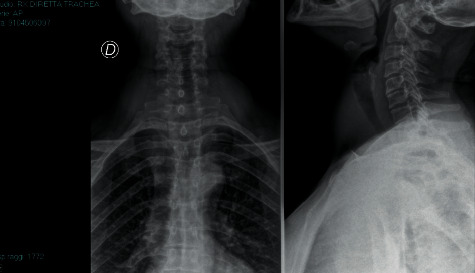

在清醒的患者中使用柔性纤维支气管镜插管通常被认为是预测插管困难的患者的首选技术。然而,在某些情况下,纤维支气管镜的使用并不适用,特别是由于患者自身的问题或仪器的有限使用。在这种情况下,视频喉镜可以是一个有用的选择,只要它与患者足够的镇静有关。事实上,它可以确保对声门的良好观察,即使在气道困难的情况下也可以成功地进行口气管插管,同时在整个过程中保持患者自主呼吸。从现有的文献资料来看,该技术似乎确保了与纤维支气管镜相似的成功率和安全性,而且麻醉师更容易使用。这项工作的主要目的是为那些预期气道管理困难且因不同原因不能使用纤维支气管镜的患者提供一种有效且安全的清醒时纤维支气管镜插管替代方法。

Intubation with a flexible fibrobronchoscope in an awake patient is frequently considered the technique of choice in patients with predicted difficult intubation. There are, however, situations in which the use of the fibrobronchoscope is not applicable, particularly due to problems attributable to the patient or to limited use of the instrument. In such situations, the video laryngoscope can be a useful alternative, as long as it is associated with adequate sedation of the patient. In fact, it ensures excellent viewing of the glottis, allowing for successful orotracheal intubation to be performed even in case of difficult airways, while keeping the patient spontaneously breathing throughout the procedure. From the data present in the literature, this technique seems to ensure a success rate and a safety profile similar to those obtained with the fibrobronchoscope, moreover, with greater ease of use by the anaesthesiologist. The main purpose of this work is to provide a valid and safe alternative to intubation with a fibrobronchoscope while awake in those patients with anticipated difficult airway management and in whom, for different reasons, fibrobronchoscope cannot be used.